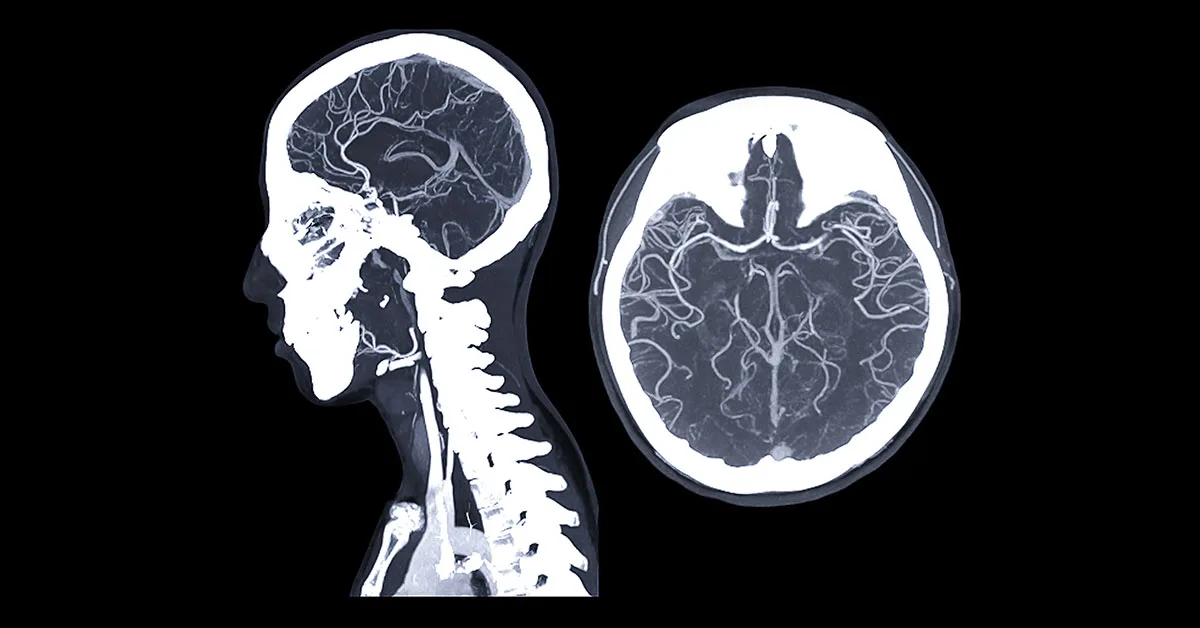

Angiotomografia do crânio

A angiotomografia de crânio é frequentemente solicitada em conjunto com a angiotomografia cervical para estudo da circulação carotídea, vertebral e intracraniana.

As imagens podem revelar variações anatômicas, aneurismas, malformações arteriovenosas ou ainda um ponto de obstrução de um segmento arterial dentro da investigação de urgência de um acidente vascular encefálico isquêmico, os conhecidos AVCs ou derrames cerebrais.